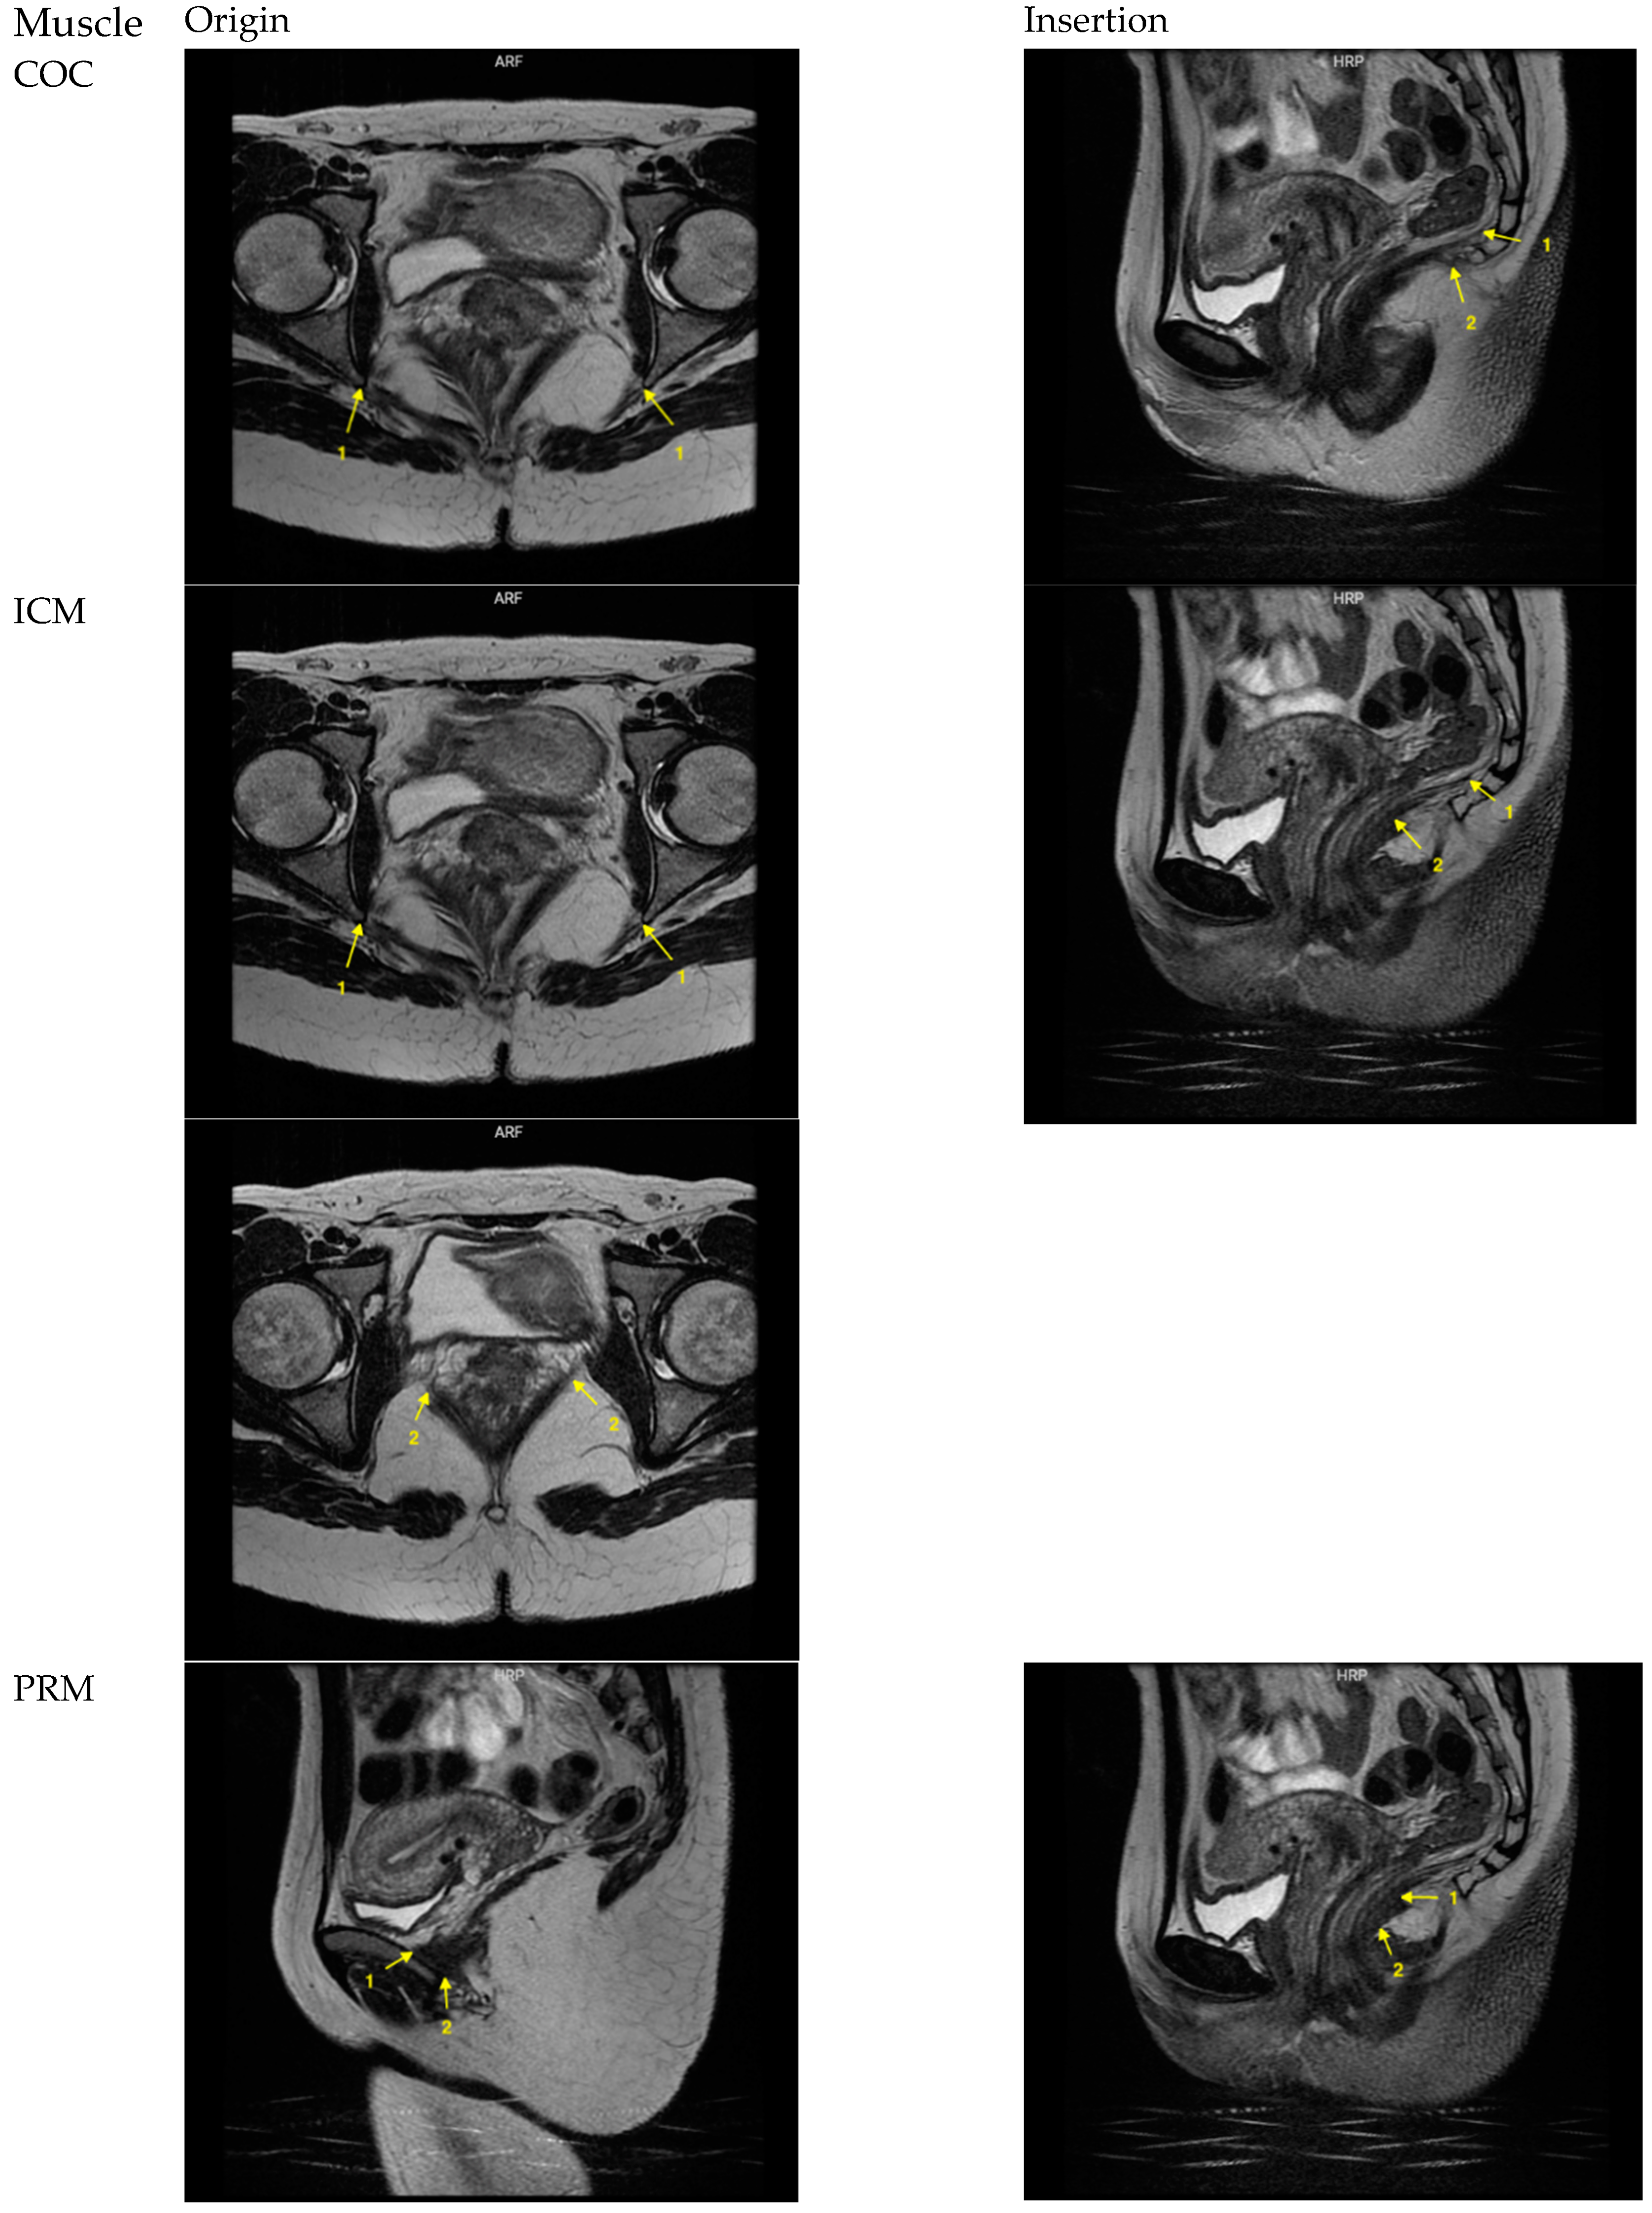

| Muscle | POI | Plane | Description | |||

|---|---|---|---|---|---|---|

| Origin | Insertion | Origin | Insertion | Origin | Insertion | |

| COC | 2 points, 1 on each side | 4 points, 2 on each side | Axial | Sagittal | Originating from the ischial spine, most cranial and most posterior point | Parasagittal, inserting at the coccyx 1: most cranially visible muscle fibers 2: most caudally visible muscle fibers |

| ICM | 4 points, 2 on each side | 2 points, in the midline | Axial | Sagittal | Originating from the tendinous arch of the LAM 1: most cranial and most posterior point, originating from the ischial spine 2: most anterior point, transitioning to obturator muscle | Midsagittal, inserting in the iliococcygeal raphe 1: most cranial 2: most caudal |

| PRM | 4 points, 2 on each side | 2 points, in the midline | Sagittal | Sagittal | Parasagittal, originating from pubis 1: most anterior 2: most posterior | Midsagittal, forming a sling behind the rectum and manifesting as a bump 1: most cranially visible muscle fibers 2: most caudally visible muscle fibers |